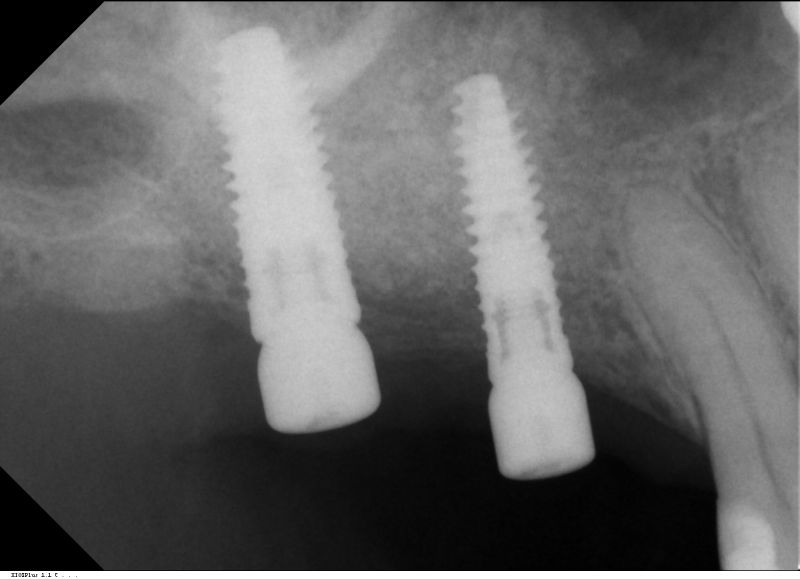

Horizontal ridge augmentation with maxgraft® cortico - M.Sc. E. Kapogianni

OPG of the initial situation – provision of missing denture in regio 44 to 47 by a resin-retained bridge